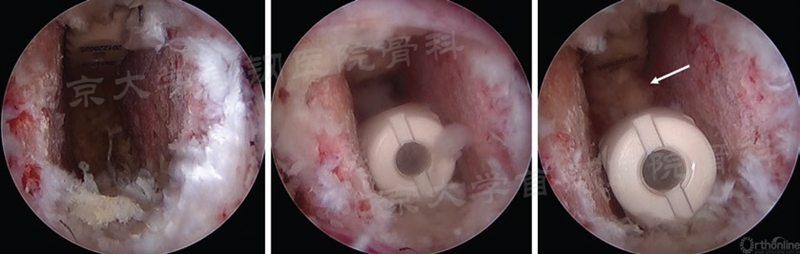

(2)单侧双cage融合术:入路同TLIF,处理好椎间隙后,同侧植入cage后将其打入至对侧,然后再植入一枚cage(如图23)。

图23 单侧双cage融合术植入两枚cage的镜下过程(图片来源于书籍)